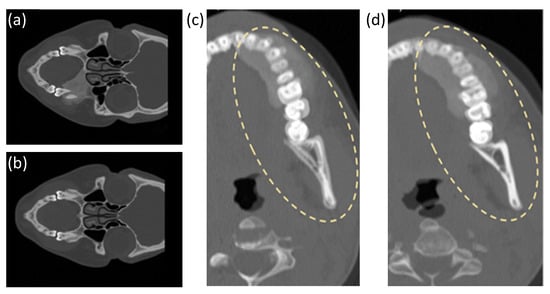

2.2. Orthopaedic Applications

3.2. Case Study 2: Landmark Registration in Orthopaedics

4.2. Case Study 2